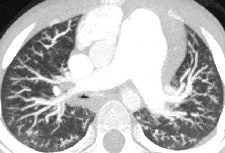

CT is vital for evaluating the central airway, mediastinal structures, and lung parenchyma, plus it's more sensitive than plain radiographs in detection of structural changes within the lungs, but CT examinations must be clinically justified by the referring clinician and radiologist.

MDCT using a low radiation dose protocol is the best diagnostic tool for assessing the central airway, cardiovascular and mediastinal abnormalities, and the lung parenchyma in children, and the relevant information can be acquired with a single-volumetric data set acquisition, she stated. Using thin-slice collimation acquisition with inherent isotropic resolution, the image data can be manipulated and reformatted to display 2D and 3D images with the same spatial resolution as the axial images, thus enhancing diagnostic accuracy and providing data that can be used in presurgical planning and patient management.